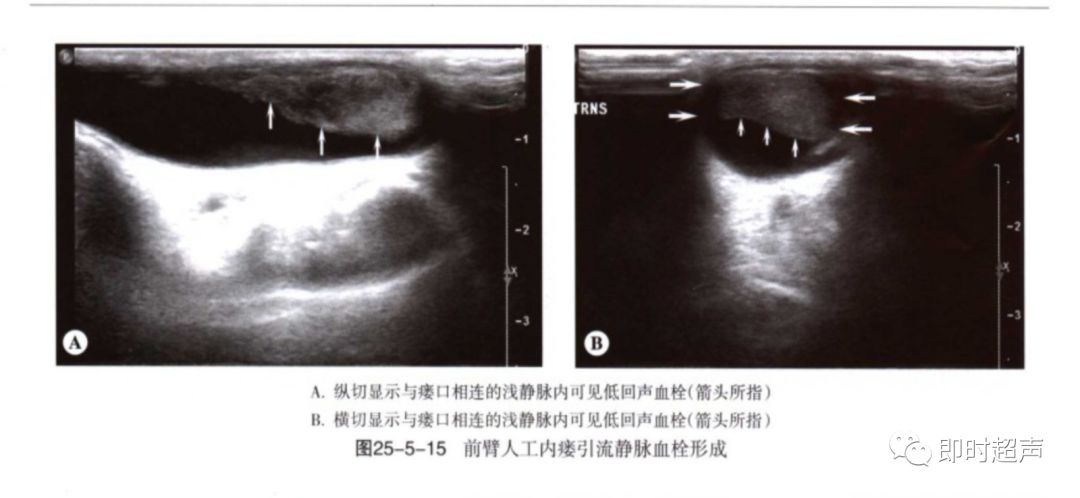

血栓:血栓与狭窄密切相关,常发于静脉侧,静脉管腔压瘪可除外血栓形成。闭塞处可见彩色多普勒血流中断,频谱多普勒信号消失。流入道动脉呈高阻频谱改变。